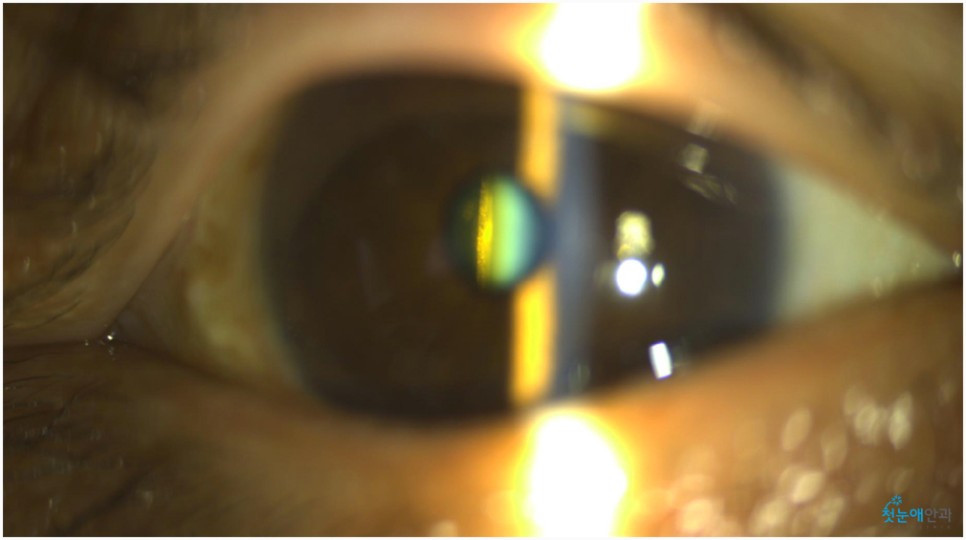

노안 수술 안과에 내원하셨을 때 오른쪽 눈이 잘 보이지 않는다고 말씀하셨습니다.이에 첫눈 애안과 장비를 통해 조사한 결과 이미 백내장 진행이 상당하고 눈 밑 망막 관찰이 어려울 정도로 흐릿한 상태였습니다.

눈이 침침해서 잘 보이지 않았던 것은 올해 초부터라고 말씀하셨습니다.진단 결과 백내장 B) N5CO(+++) PSC(+++) 단계에 해당되며 이는 매우 심한 정도여서 예전에는 맑은 수정체였으나 지금은 혼탁하고 진한 갈색으로 바뀌었습니다.참고로 백내장 초기라면 약물 사용으로 진행을 늦출 수 있었을 것 같은데, 노안수술안과를 방문해주신 환자들은 너무 많은 진행이 있었기 때문에 수술이 필요했습니다.

백내장이 상당히 진행되면 수정체가 흐려져 눈 아래의 망막 관찰이 어렵습니다.때문에 사진을 찍어 검사해봐야 하는데 위와 같이 흐릿한 사진이 찍혀 사실상 망막 관찰이 어렵습니다.뿐만 아니라 심한 백내장은 부분마취 수술 진행이 어려워 안구마취나 전신마취로 수술하거나 종합병원으로 전환해 수술해야 합니다.뿌옇게 변했는데도 그냥 놔두면 위 사진처럼 더 심해져 시력이 저하되는 상황까지 이어지게 됩니다.